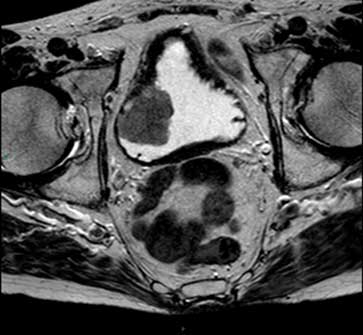

Hình 2. Hình ảnh MRI xung T2 cắt ngang cho thấy một khối u bên phải,đồng thời cho thấy u chưa lan ra ngoài bàng quang.

Hình ảnh T2 nên được thu thập hoặc tái tạo trong ba mặt phẳng. Hình ảnh T2 cho phép đánh giá khối u nguyên phát và thành bàng quang (Hình 2) và vượt trội hơn so với hình ảnh T1 trong việc đánh giá sự xâm lấn vào các cơ quan lân cận như tuyến tiền liệt hoặc tử cung. Cũng như phim cắt ngang (axial), một khối u bàng quang ở thành bên hoặc ở vòm được đánh giá tốt nhất trên phim cắt đứng ngang (coronal) và một khối u phía trước ở mặt phẳng đứng dọc (sagittal).